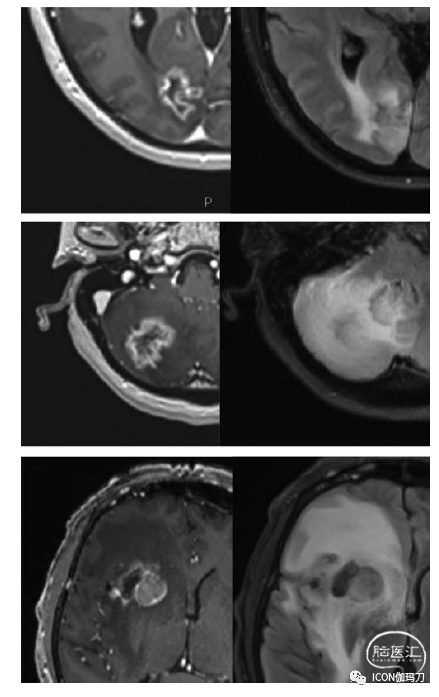

考虑到MRI分析依赖于血脑屏障的通透性,通常有对肿瘤复发和放射性坏死两者难以区分的影像学改变。恶性肿瘤通常会导致血脑屏障破坏,使钆剂离开血管内空间进入组织,从而在成像上增强对比度(This often shows indistinguishable imaging changes for both tumor recurrence and radiation necrosis, given the reliance of MRI analysis on the permeability of the BBB. Malignancy typically causes BBB breakdown allowing the gadolinium dye to leave the intravascular space and enter the tissues resulting in contrast enhancement on imaging.)。放射性坏死,作为一种炎症过程,同样会破坏血脑屏障,在MRI对比扫描上显示类似的增强。因此,在这两种病理中,钆剂增强T1加权MRI显示病变边缘强化,中心区域无强化被认为是坏死。所有的放射性坏死病例中都可见中央坏死在,但许多肿瘤也包含明显的坏死区域,这进一步混淆了影像学的解释。肿块占位效应可能是由于病变本身,或者更多的是由于广泛的病变周围脑水肿,被视为周围大范围的液体衰减反转恢复(FLAIR)信号异常,这在肿瘤坏死和放射性坏死中是相同的。虽然已有充分的文献证明,使用病变形态学往往不足以区分这两种诊断,但在日常实践中,许多肿瘤会表现为实质性圆形的再生长区,一些放射性坏死病变会表现出“伪足”、“瑞士奶酪”、“切甜椒”或“肥皂泡”的特征变化(“pseudopodic,” “Swiss cheese,” “cut bell pepper,” or “soap bubble” changes),这是Kumar等最初描述的,可用于诊断(图36.1)。虽然尚未发现脑叶或小脑幕上与小脑幕下的位置与发生RN的风险相关,但根据我们的医院经验,脑室周围的位置似乎增加了RN的风险。最后,Sneed等报道,在治疗的2200个转移瘤病灶中,病灶再生长活检显示9.2%的肿瘤复发,5.4%的孤立性放射性坏死,1.4%的肿瘤复发和坏死合并。研究发现,在一定比例的患者中,这些病变包含放射性坏死和肿瘤组织的成分,这进一步复杂化了诊断,并说明需要更详细的空间成像。

图36.1(第1行)SRS治疗后18个月肺癌患者T1加权钆增强轴位MRI显示假足改变,并伴有病灶周围T2 FLAIR改变增加,提示RN病变。(第2行)同一患者第2病灶T1加权钆MRI切甜椒变化,其周围脑水肿比例较高。(第3行)相比之下,SRS治疗后2年的黑色素瘤患者在T1加权钆剂MRI上发现临近RN的结节性生长和周围明显的FLAIR信号改变。